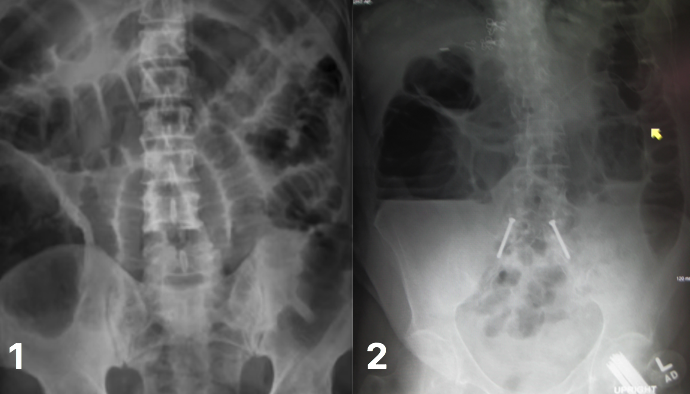

What is shown in image 1?

Bowel obstruction on AXR; small bowel obstruction, showing valvulae conniventes crossing a dilated, centrally-located bowel.

What is shown in image 2?

Bowel obstruction on AXR; large bowel obstruction, with peripherally located dilated bowel segments.